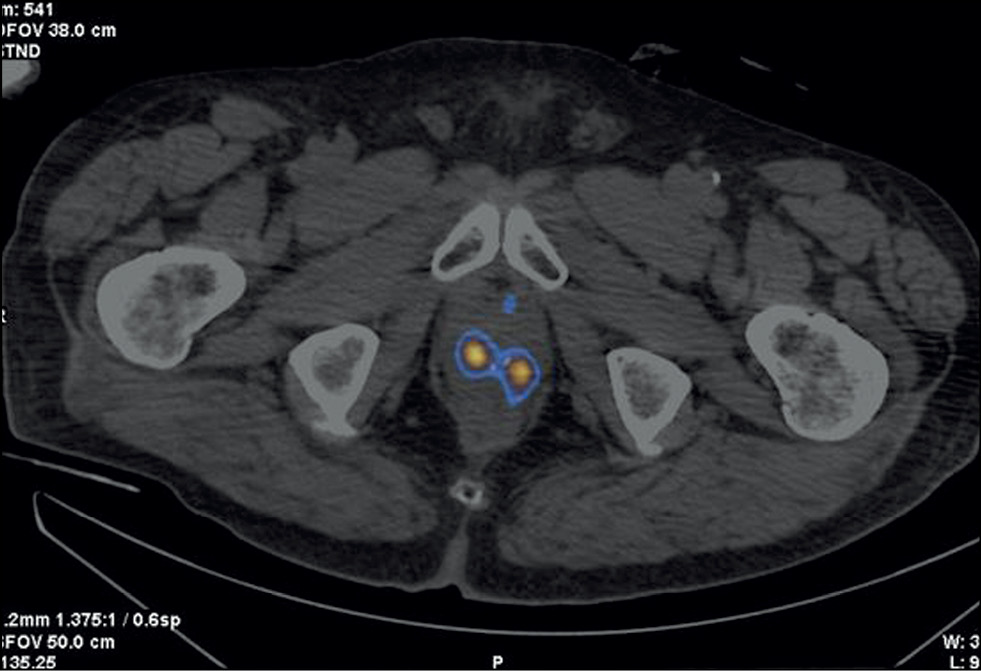

Patient Z., 79 years old, was admitted with diffuse prostatic hyperplasia. PSA level was 4.5 ng/mL. No abnormal lesions were found in the prostate tissue using ultrasound, TRUS, and contrast-enhanced MRI. SPECT/CT with 99mTc-HYNIC-PSMA revealed 15-mm3 sites of RP accumulation in the prostate tissue (Figure 3). Because rectal amputation made US-guided prostate biopsy impossible, a targeted CT-guided biopsy was performed pararectally. A morphological diagnosis was adenocarcinoma, Gleason 6 (3 + 3).

Fig. 3. Patient Z., 7 years old, SPECT/CT with 99mTc-HYNIC-PSMA: Sites of radiopharmaceutical accumulation in transitory zones of both lobes at the border of the middle third and the apex of the prostate gland.

On January 28, 2021, 125I sources were implanted pararectally under a CT guide. In the follow-up examination, PSA levels were 0.2 ng/mL (September 2022) and 0.1 ng/mL (January 14, 2023).

In this case, two problems were revealed: an unknown cause of increased PSA over time and the inability to perform a targeted prostate carcinoma biopsy under US guide. Both problems were successfully resolved using hybrid SPECT/CT with 99mTc-HYNIC-PSMA followed by CT-guided RP accumulation site biopsy, and precision brachytherapy was performed with a smaller number of 125I microsources due to the SPECT/CT pattern.